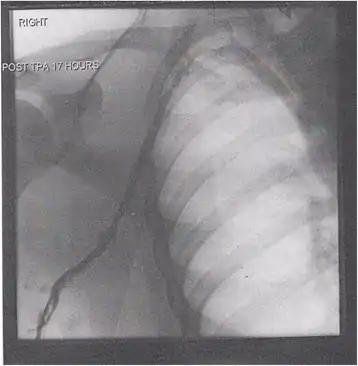

Thrombolysis is the injection of an enzyme into the veins to dissolve blood clots, and while this treatment has been proven effective against the life-threatening emergency clots of stroke and heart attacks, randomized controlled trials[139][140][141] have not established a net benefit in those with acute proximal DVT.[5][142] Drawbacks of catheter-directed thrombolysis (the preferred method of administering the clot-busting enzyme[5]) include a risk of bleeding, complexity,[lower-alpha 12] and the cost of the procedure.[125] Although, while anticoagulation is the preferred treatment for DVT,[125] thrombolysis is a treatment option for those with the severe DVT form of phlegmasia cerula dorens (bottom left image) and in some younger patients with DVT affecting the iliac and common femoral veins.[12] Of note, a variety of contraindications to thrombolysis exist.[125] In 2020, NICE kept their 2012 recommendations that catheter-directed thrombolysis should be considered in those with iliofemoral DVT who have "symptoms lasting less than 14 days, good functional status, a life expectancy of 1 year or more, and a low risk of bleeding."[138]

A mechanical thrombectomy device can remove DVT clots, particularly in acute iliofemoral DVT (DVT of the major veins in the pelvis), but there is limited data on its efficacy. It is usually combined with thrombolysis, and sometimes temporary IVC filters are placed to protect against PE during the procedure.[143] Catheter-directed thrombolysis with thrombectomy[141] against iliofemoral DVT has been associated with a reduction in the severity of post-thrombotic syndrome at an estimated cost-effectiveness ratio of about $138,000[lower-alpha 13] per gained QALY.[144][145] Phlegmasia cerulea dolens might be treated with catheter-directed thrombolysis and/or thrombectomy.[19][143]